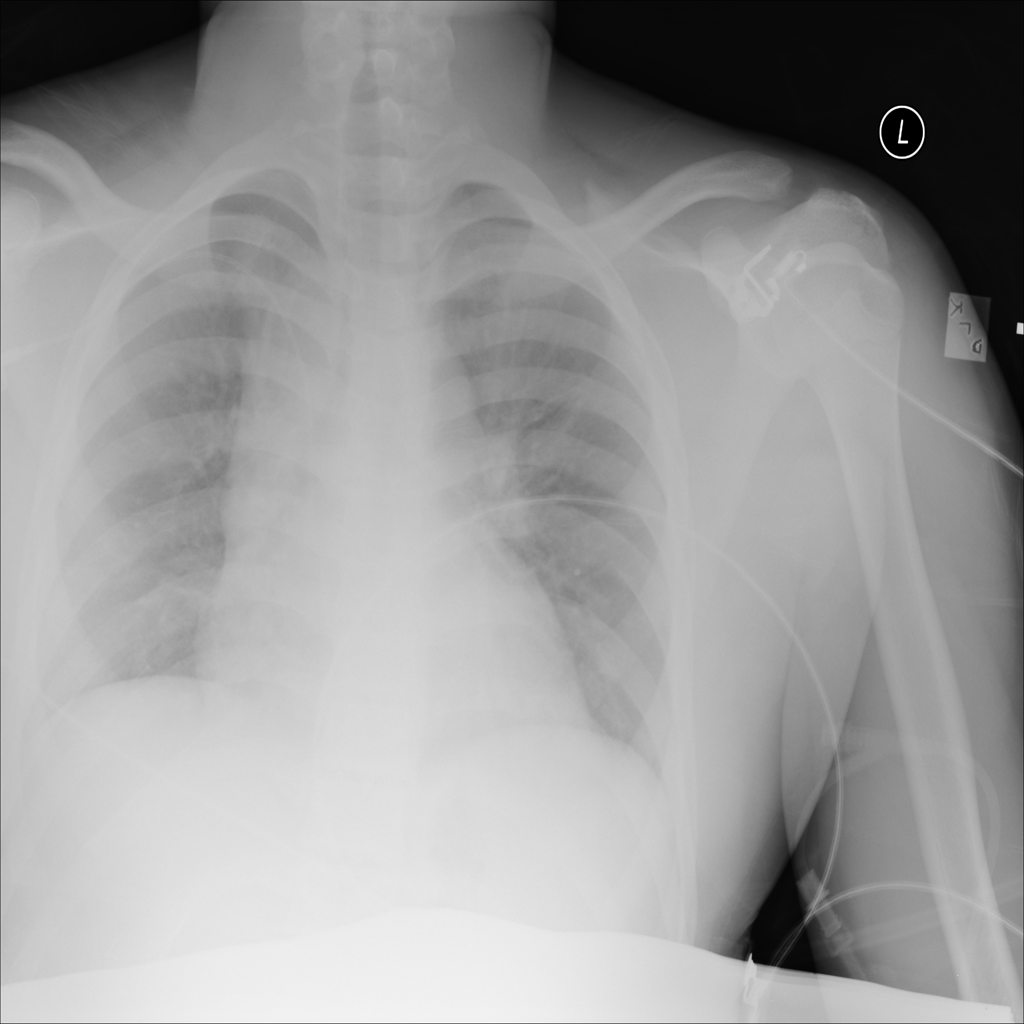

Mass

A mass is a larger focal opacity or lesion seen on the image. It is a descriptive finding that can have several causes and usually needs more imaging or clinical context to characterize.

PAT-50E5 · IMG-008Mass

PAT-50E5 · IMG-008

PA